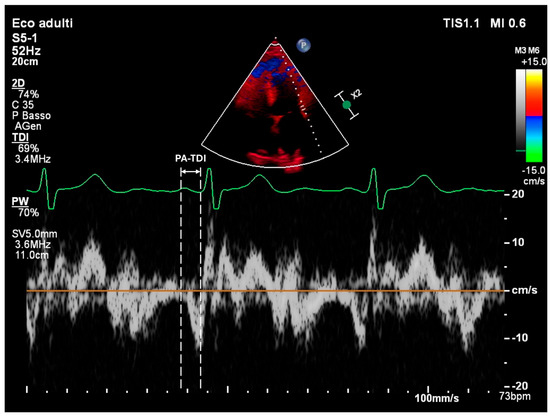

| PA-TDI | Atrial Conduction Time Measured by Tissue Doppler Imaging |

- Müller, P.; Weijs, B.; Bemelmans, N.M.A.A.; Mügge, A.; Eckardt, L.; Crijns, H.J.G.M.; Bax, J.J.; Linz, D.; den Uijl, D.W. Echocardiography-derived total atrial conduction time (PA-TDI duration): Risk stratification and guidance in atrial fibrillation management. Clin. Res. Cardiol. 2021, 110, 1734–1742. [Google Scholar] [CrossRef]

- Karantoumanis, I.; Doundoulakis, I.; Zafeiropoulos, S.; Oikonomou, K.; Makridis, P.; Pliakos, C.; Karvounis, H.; Giannakoulas, G. Atrial conduction time associated predictors of recurrent atrial fibrillation. Int. J. Cardiovasc. Imaging. 2021, 37, 1267–1277. [Google Scholar] [CrossRef]

- Müller, P.; Schiedat, F.; Bialek, A.; Bösche, L.; Ewers, A.; Kara, K.; Dietrich, J.W.; Mügge, A.; Deneke, T. Total atrial conduction time assessed by tissue doppler imaging (PA-TDI Interval) to predict early recurrence of persistent atrial fibrillation after successful electrical cardioversion. J. Cardiovasc. Electrophysiol. 2014, 25, 161–167. [Google Scholar] [CrossRef]

- Chiotis, S.; Doundoulakis, I.; Pagkalidou, E.; Piperis, C.; Zafeiropoulos, S.; Botis, M.; Haidich, A.B.; Economou, F.; Chierchia, G.B.; de Asmundis, C.; et al. Total Atrial Conduction Time as a Predictor of Atrial Fibrillation Recurrence: A Systematic Review and Meta-Analysis. Cardiol. Rev. 2025, 33, 70–76. [Google Scholar] [CrossRef] [PubMed]